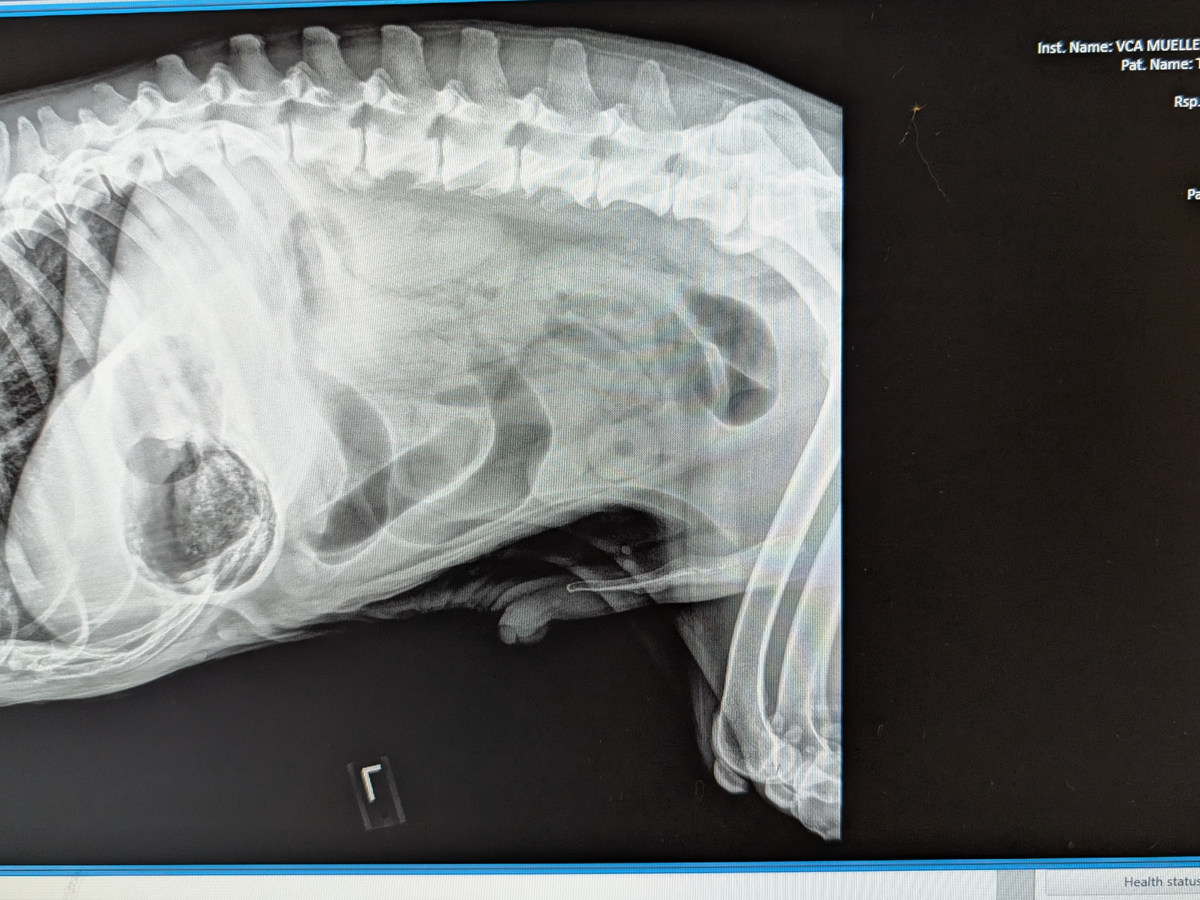

Hello, my name is Destiny and my fiance's name is Natasha she goes by Tasha we are in need of help raising funds to get surgical treatment for our very beloved CAPONE he's our 12 year old senior American Bulldog he's my fiance's BEST FRIEND LITERALLY. Her main man! Everyone who's met Capone falls in love he's just the sweetest boy you could ever meet! A while ago he started acting extremely lethargic, not eating, not sitting down and not very alert at all.. We took him to the vet and they have charged us $1,500 for X-rays and blood work to find that he has a blockage in his stomach and we desperately need help to save him and get him into surgery! Please, if you find it in your heart to help in any way we would greatly appreciate it. My birthday is also tomorrow 05/31 this would be the best birthday gift!! <3 I couldn't imagine not saving him.